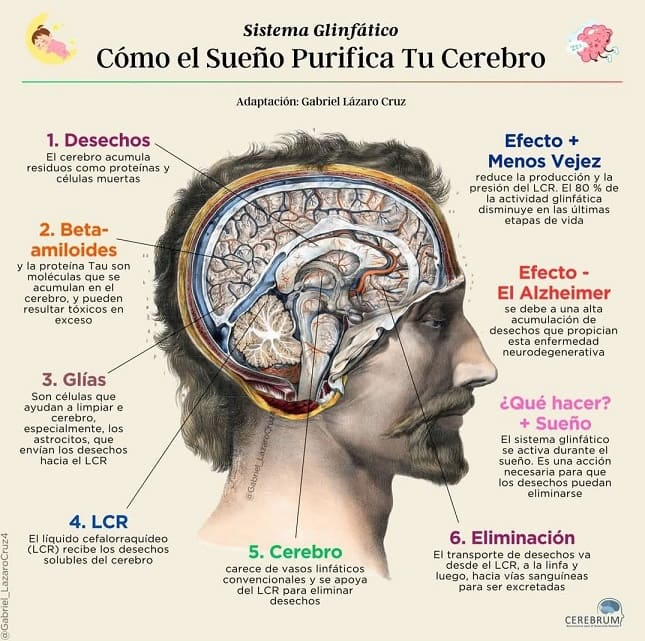

- Este veneno está en su sangre y tejidos: actúe ahora para expulsarlo